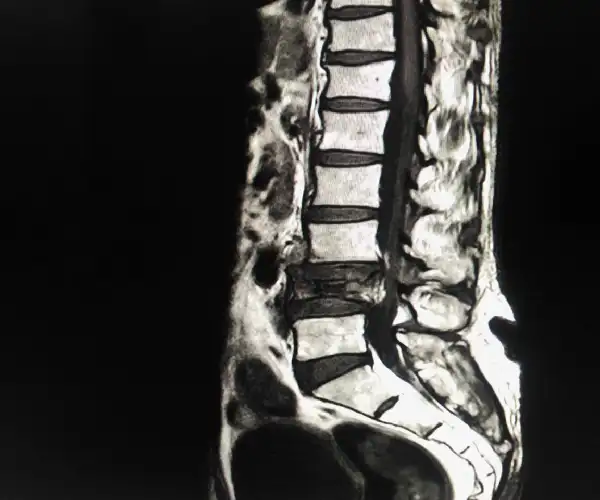

Pathological Collapse Of L4

CT Showing Diastem